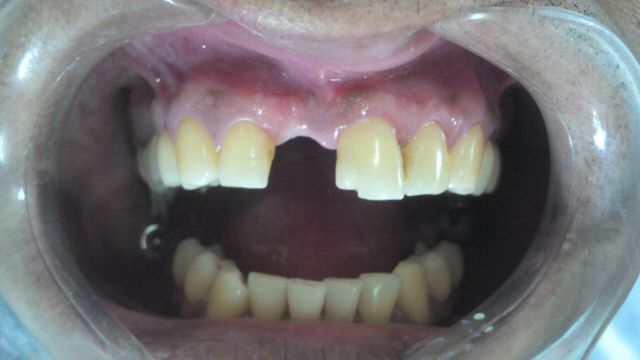

Observem: nesse caso o paciente perdeu o incisivo central superior direito e necessitava de um implante dentário.

Porém, quando se perde um dente, o nosso organismo reabsorve o osso alveolar e ele fica menor em altura e espessura.

Como colocar um implante nessa situação? Ainda que se possa instalar o implante, a prótese não ficará adequada, esteticamente perfeita. O resultado será péssimo.